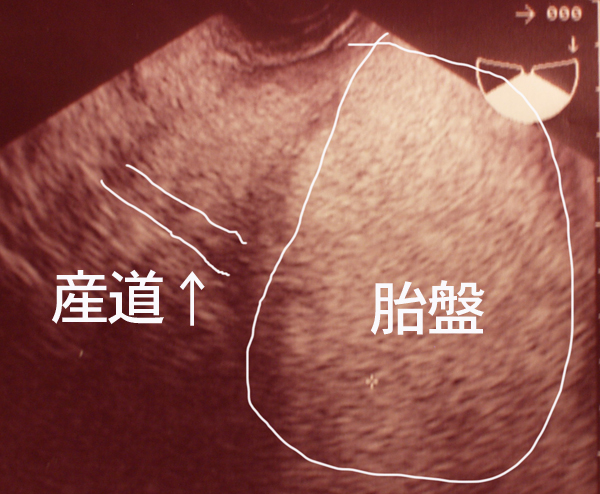

↓これが胎盤ばっかりで全然見えないエコー。

ちなみに、転院指示の日のエコーでは

産道の先にお尻どころか

胎盤がどーーーんとあって影になってしまい

産道もよく見えないし、子供ももちろん見えない。

完全に胎盤しかみえない!という状態でした。